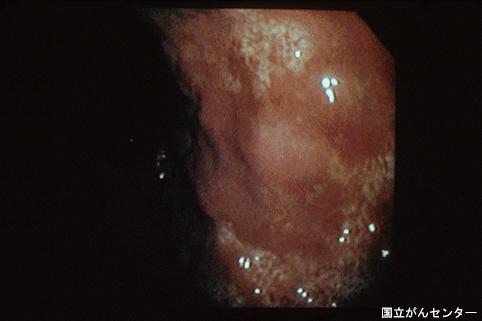

유방암의 수술로 부터 4년 후에、위에 미만성 전이를 일으킨 증례(다지점 합동 소화관 텔레이미지 컨퍼런스 증례)

TIC 증상예(다지역 합동소화기관 텔리 이미지 협의회)

질환(병리주체)의 분류

전이성종양/

부위(장기별)

위(부위)/2개 이상

검사방법

내시경

종양의 육안분류

4형(미만침윤형)/

종양의 최대경(밀리미터)

40이상

종양의 심달도

s(a)

다발종양(동일 장기)

무

다중종양(다수의 장기)

유(이시성)